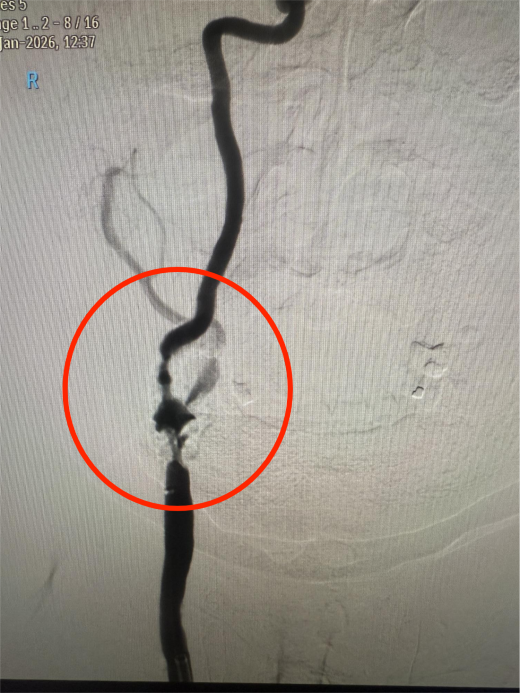

上图为该患者手术前重度狭窄的血管

传统药物保守治疗难以从根本上解决血管狭窄问题,无法有效规避脑梗死的风险。面对这一棘手局面,血管介入科马心龙副主任决定组织一场疑难病例讨论,同时邀请呼吸科、心内科、重症医学科等科室专家开展多学科会诊,全面评估患者的身体状况、血管条件及手术耐受性。同时,反复推演手术流程,细致排查术中可能出现的血压骤变、心律失常、斑块脱落、脑血管痉挛等风险点,并制定了针对性的应急处理方案。